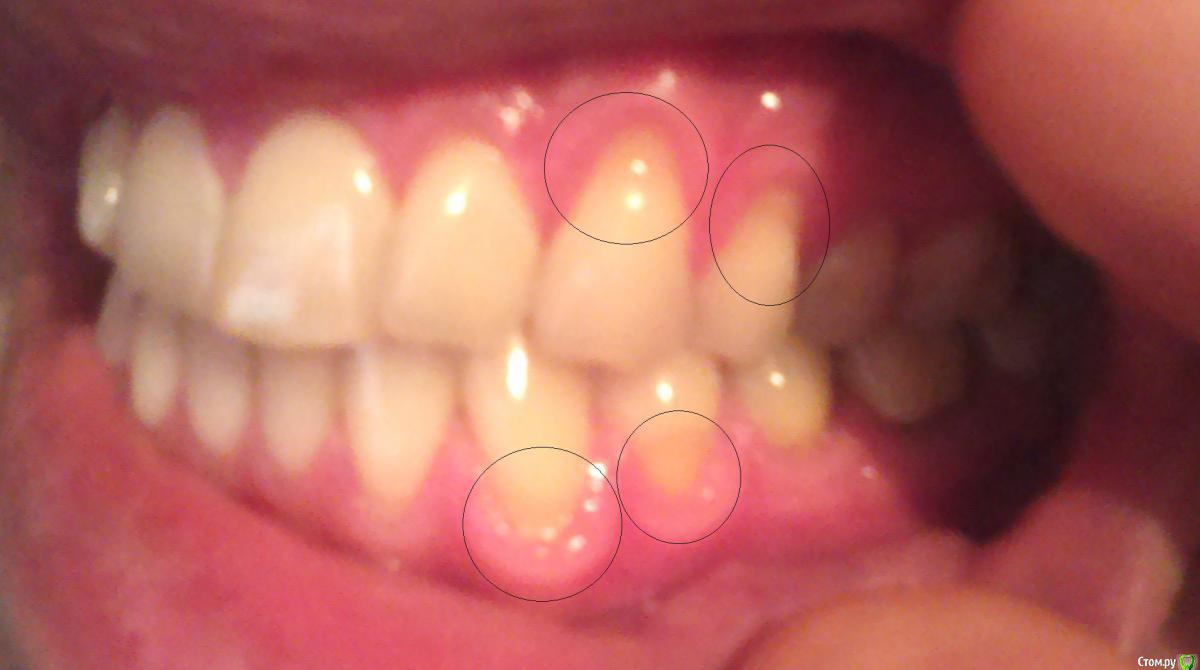

Bizzzin Опубликовано 7 декабря, 2015 Автор Поделиться Опубликовано 7 декабря, 2015 Конечно! В приложении направляю фотографии. Ссылка на комментарий

red_butler Опубликовано 8 декабря, 2015 Поделиться Опубликовано 8 декабря, 2015 Это рецессии десны, причина скорее всего в механической травме зубной щеткой. Закрываются они хирургическим путем. 3 Ссылка на комментарий